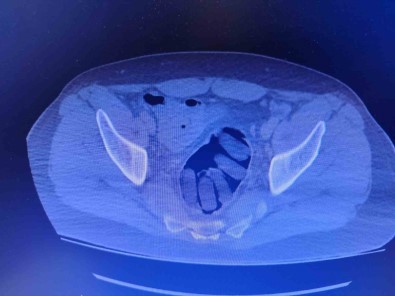

Kirsehir Il Emniyet Müdürlügü Narkotik Suçlarla Mücadele Sube Müdürlügü ekipleri tarafindan yapilan çalismalarda yabanci uyruklu Y.S. ve H.S.’nin dogu illerinden ülkeye kaçak yollarla girdikleri ve bati illerine uyusturucu madde kuryeligi yaptiklari tespit edildi. Takibe alinan uyusturucu kuryelerinin seyahat ettigi yolcu otobüsü Kirsehir’de durduruldu. Gözaltina alinan ve hastaneye götürülen sahislarin midelerinde kapsül bulundugu tespit edildi. Sahislarin midelerinde zulaladigi 126 kapsül halinde 1 kilo 300 gram ve 44 kapsül halinde 550 gram uyusturucu madde ele geçirildi.